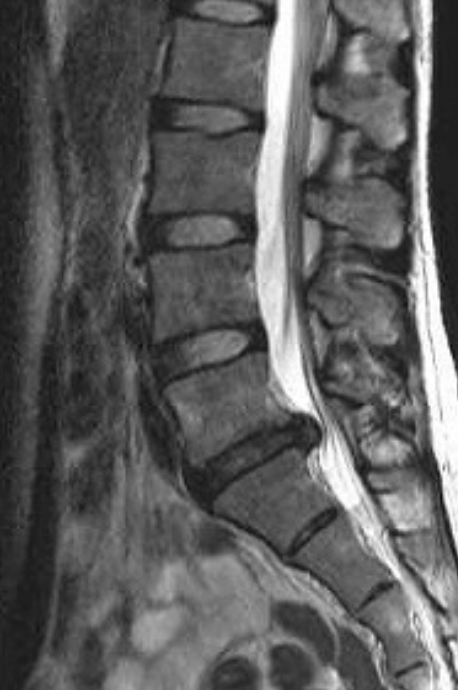

腰椎椎間板ヘルニアの治療法 腰椎椎間板ヘルニア ドクター S コラム Eo健康

腰椎椎間板ヘルニア の症状やリハビリ方法について解説 御所南リハビリテーションクリニック

腰椎椎間板ヘルニアの原因と解消法を詳しく解説 たけだ整体院 整骨院